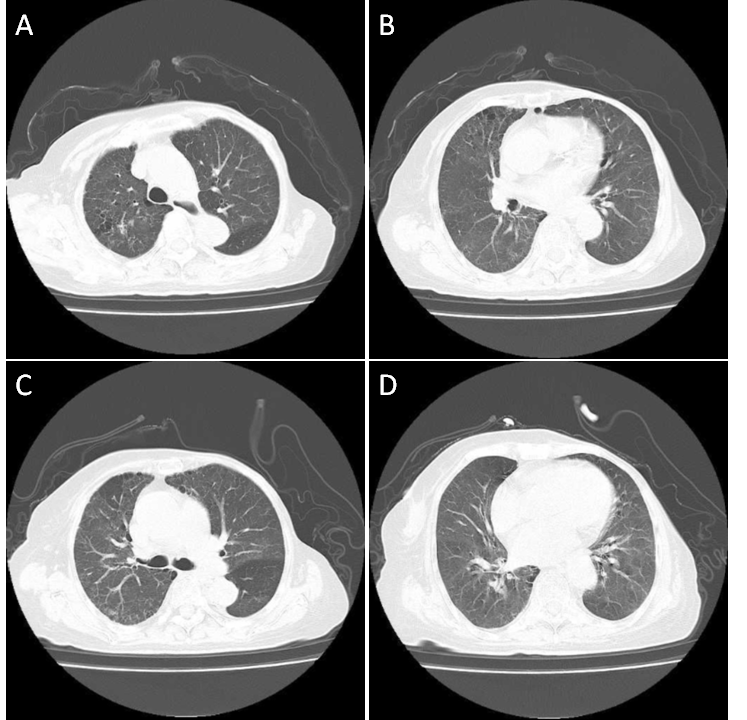

附图

1A

和

1B

(

2022-04-14

)胸部

CT

平扫示

双肺炎症基本吸收,无明显病灶,纵隔基本居中;

1C

1D

2022-05-11

双肺散在炎症,较

进一步改善